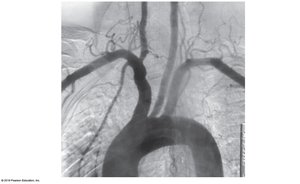

Branches of the subclavian and thoracic aorta supply the thorax, while the abdominal aorta gives rise to several paired and unpaired branches supplying abdominal organs.

Unpaired branches: Celiac trunk, superior mesenteric, inferior mesenteric arteries

Paired branches: Inferior phrenic, suprarenal, renal, gonadal, lumbar arteries

Arterial Supply to the Lower Limb

The abdominal aorta divides into the right and left common iliac arteries, which further branch to supply the pelvis and lower limbs (internal and external iliac, femoral, popliteal, tibial arteries).